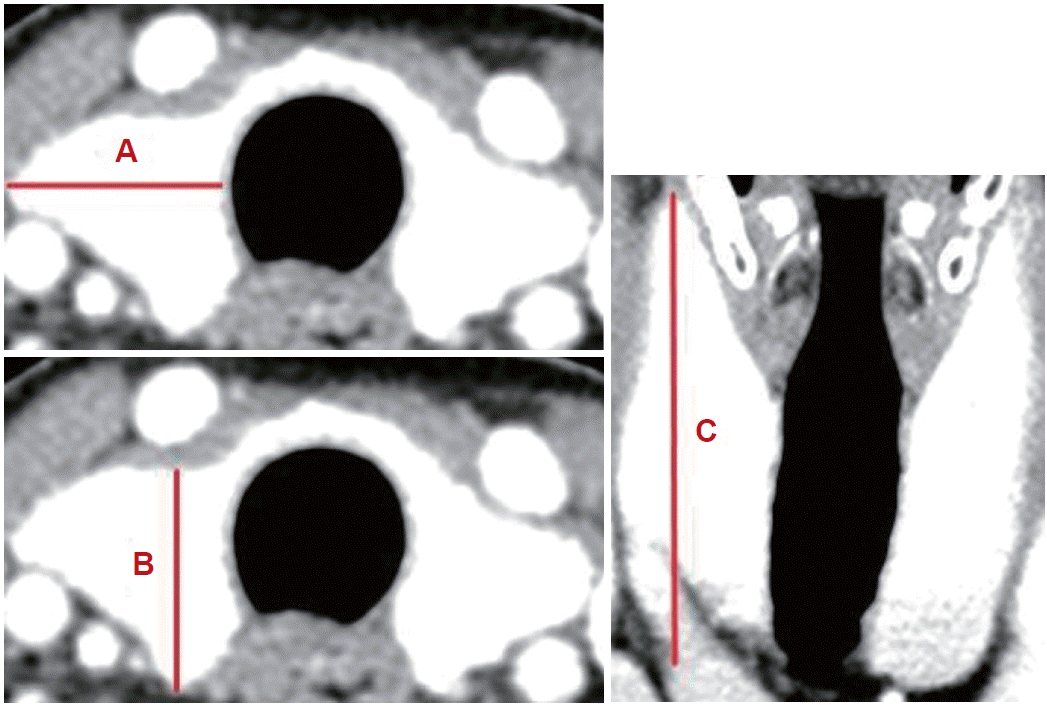

본 연구에서는 갑상선의 부피가 커질 경우에도 수술 범위가 커질 수 있으며 이는 수술 후 출혈 및 합병증 발생과 연관이 있을 것으로 가정하여 환자들의 수술 전 갑상선 크기를 측정하였다. 경부 조영증강 전산화단층촬영(enhanced neck CT)은 수술 전 모든 환자에서 시행되는데, Shabana 등[13]은 ‘부피(volume, mL)=최대너비(width, mm)×최대 깊이(depth, mm)×최대길이(length, mm)×교정계수(0.529)’라는 CT를 사용한 갑상선 부피 측정법을 제시하였고, 본 연구에서는 이를 이용하여 갑상선 부피를 측정하였다(Fig. 1). 물론 갑상선의 모양에 따라 이와 같은 방법이 정확하지 않을 수 있으나, 각 수치의 실측값을 바탕으로 부피를 구하였기 때문에 대체로 실제 부피와 비례할 것이라 가정하였다. 편측 갑상선 절제술의 경우 수술 방향에 해당하는 일측 갑상선의 부피만 측정하였으며, 갑상선 전절제술의 경우 양측 갑상선 모두의 부피를 측정하였다.